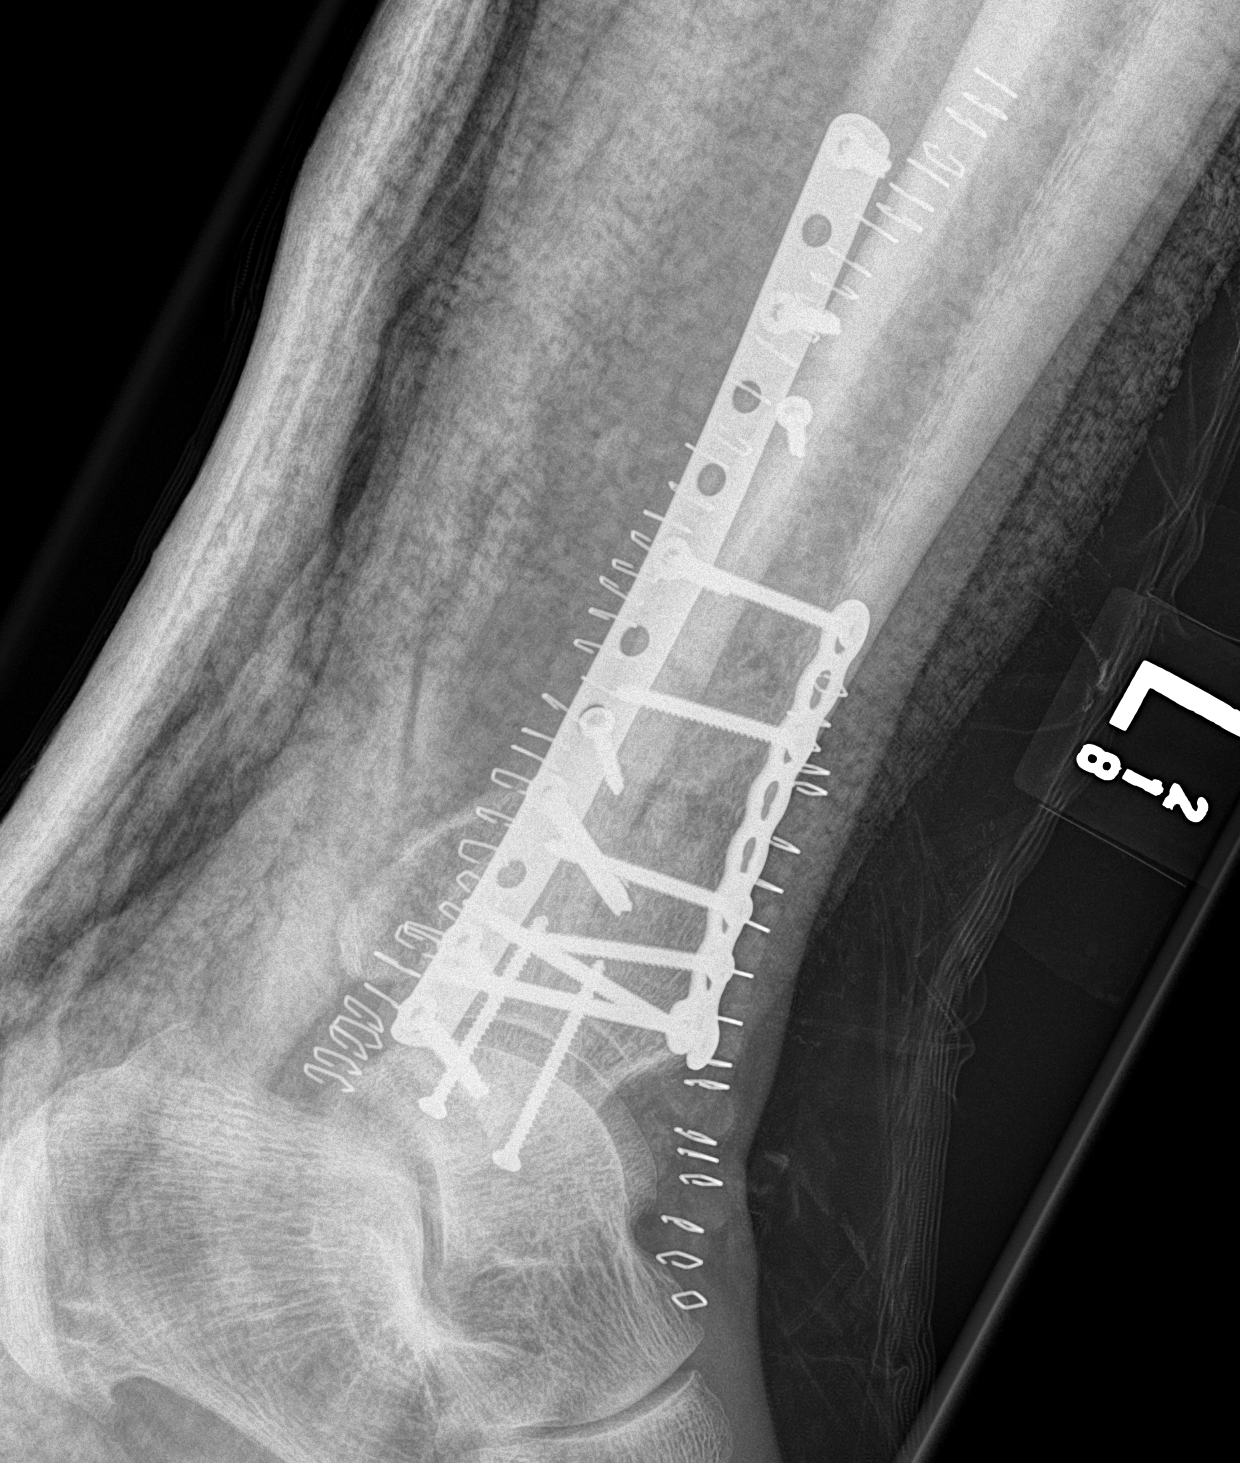

ORIF with Plates

Principle

Restore articular surface

Fix articular surface to metaphysis

Anatomical Plates

Synthes medial plate Synthes anterolateral plate

Attach metaphysis to diaphysis

- anatomically contoured low profile locking plates

- anterolateral L shaped plate via anterior wound

- small incisions proximally to insert screws

- 8 cortices above fracture

- small medial incision to insert medial plate percutaneously / MIPO techniques